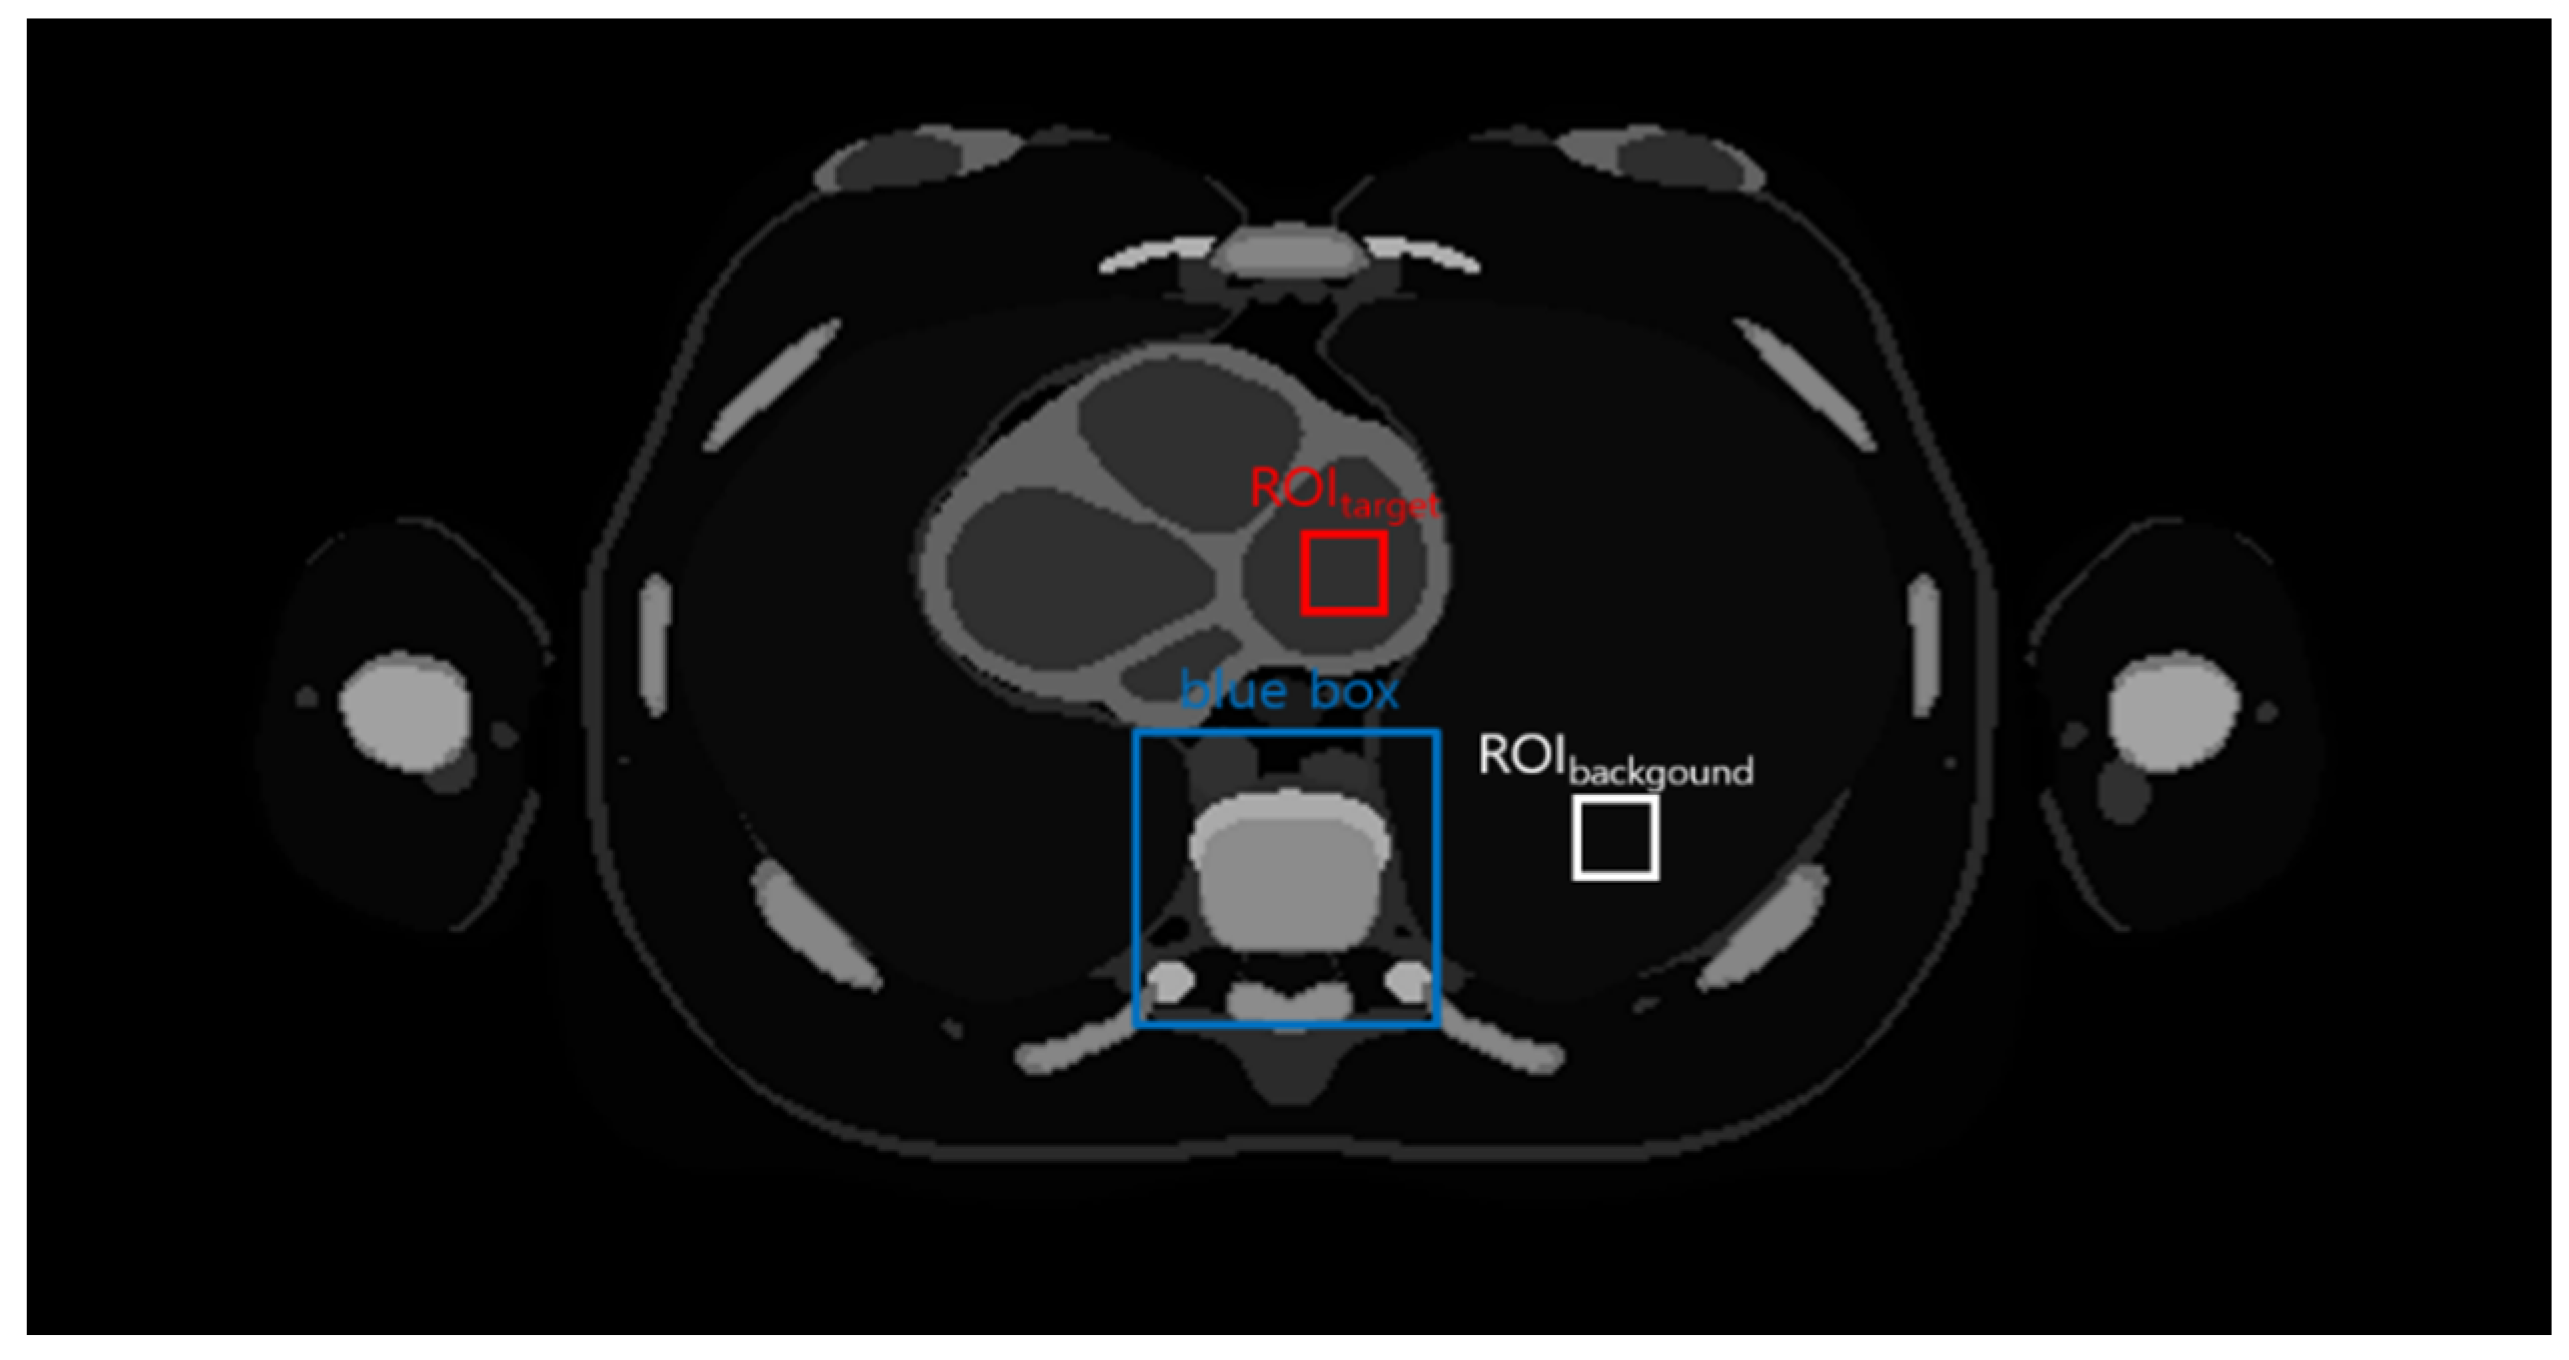

This image processing was performed using MATLAB (version R2020a, The MathWorks, Inc., Natick, MA, USA). An axial thoracic image was obtained from the CT scan dataset of the MASH phantom. Then, Gaussian noise with a standard deviation of 0.002 was added to the image. Figure 1 shows the original thoracic image with the target and background ROIs. The region within the blue box was magnified to highlight the reconstruction results. ROItarget and ROIbackground were set over the cardiac and lung regions, respectively.

Figure 1.

The image obtained from the male adult mesh (MASH) phantom. The region inside the blue box was magnified to compare the denoised images. Regions of interests (ROIs) were set to calculate the coefficient of variation (COV) and contrast to noise ratio (CNR) of the obtained chest image.